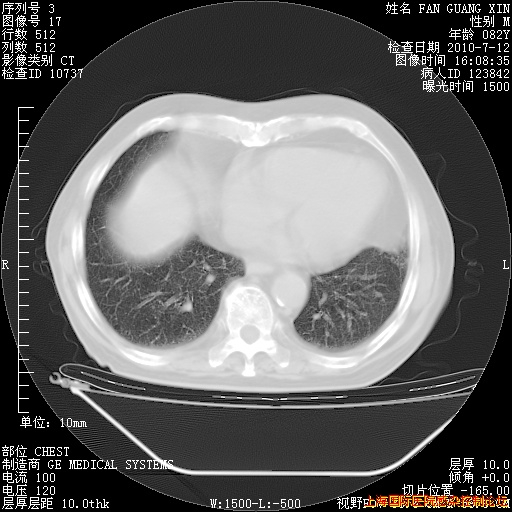

补发6月12日肺部CT肺窗

6月12日肺窗

今天复查CT

今天CT

整整相隔30天的肺部CT好像有所好转啊。甲强龙减量第3天,需要观察体温。

海管,自昨日你和我通完话后,不知您岳父消化道症状有无缓解?体温怎样?阅读7.12日胸部ct,个人认为目前激素治疗是有效的,甲强龙减量是适宜的。因在抗痨治疗,需密切观察肝功、肾功能和血常规。不过,老年、长期住院和大量使用激素,很担心菌群失调发生